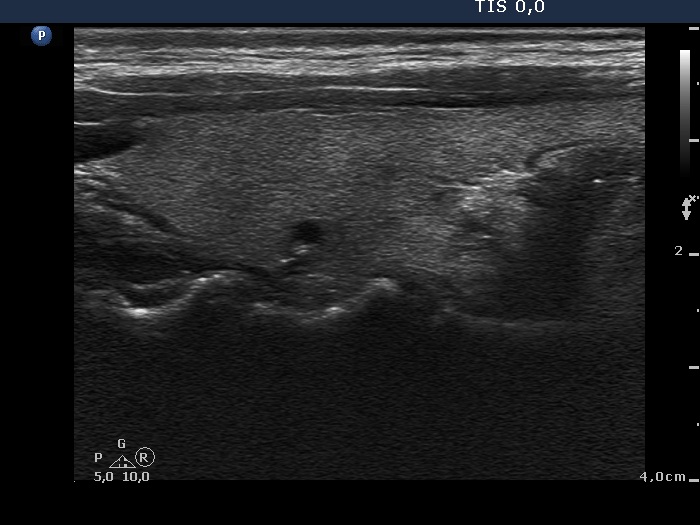

First examination (1st and 4th rows of images):

Clinical presentation: A 34-year-old woman was referred for an evaluation of neck complaints. Neck pain and fever started 2 month ago and lasted for 3 weeks. Then complaints suggesting hyperthyroidism have developed. The neck complaints have decreased. The body temperature has normalized.

Palpation: The right lobe was tender and hard on palpation.

Functional state: hyperthyroidism with TSH 0.01 mIU/L and FT4 27.2 pM/L, CRP 12.8 mg/L (normal value 0-4.8), TSAb 0 U/L.

Ultrasonography: The thyroid was echonormal and presented hypoechogenic areas with ill-defined borders. The vascularization was average.

Aspiration cytology was performed from right thyroid and resulted in subacute, granulomatous, de Quervain's thyroiditis.